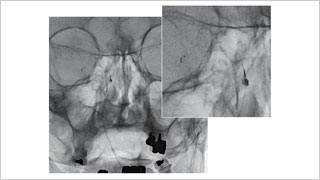

日本医科大学 脑神经外科,博慈会纪念综合医院 脑神经外科

佐藤 俊